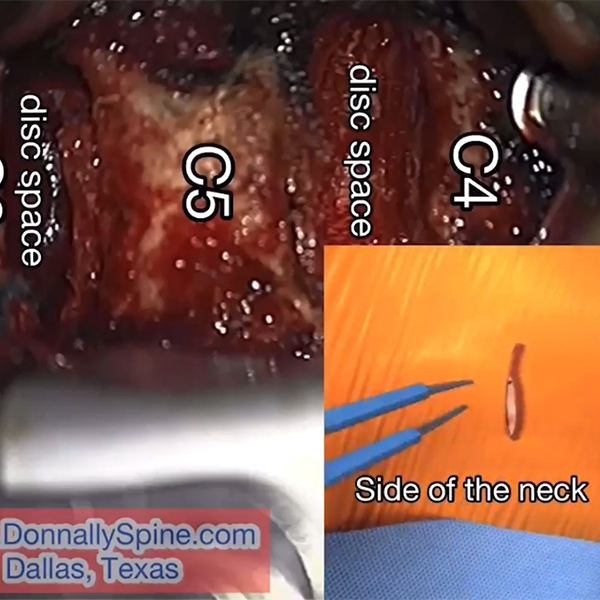

Servikal Disk Hernisi

- Mobilitemi Füzyon mu?

- Servikal Disk Hernisi Tedavi Seçenekleri

- Servikal Disk Protezi Endikasyonları

- Servikal Disk Henrisinde Füzyon

- Servikal Disk Protezinin Avantajları ve Dezavantajları

- Servikal Disk Protezi Kontraendikasyonları

- Servikal Disk Hernisi

- Patoloji

- Cerrahi Yaklaşım

- Servikal Disk Protezleri

- Servikal Spinal Çalışma Grubu

- Servikal Disk Protezi Avantajları

- Komplikasyonlar ve Olumsuz Sonuçlar

- Postoperatif Kifoz Gelişimi

- Disk Protezlerinin Dezavantajları